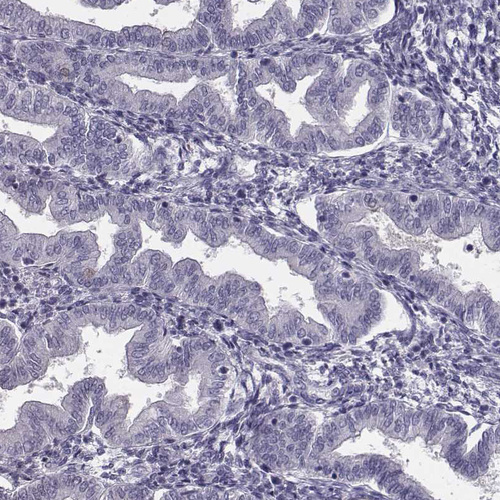

Immunohistochemistry analysis in human epididymis and endometrium tissues using HPA028445 antibody. Corresponding CRISP1 RNA-seq data are presented for the same tissues.